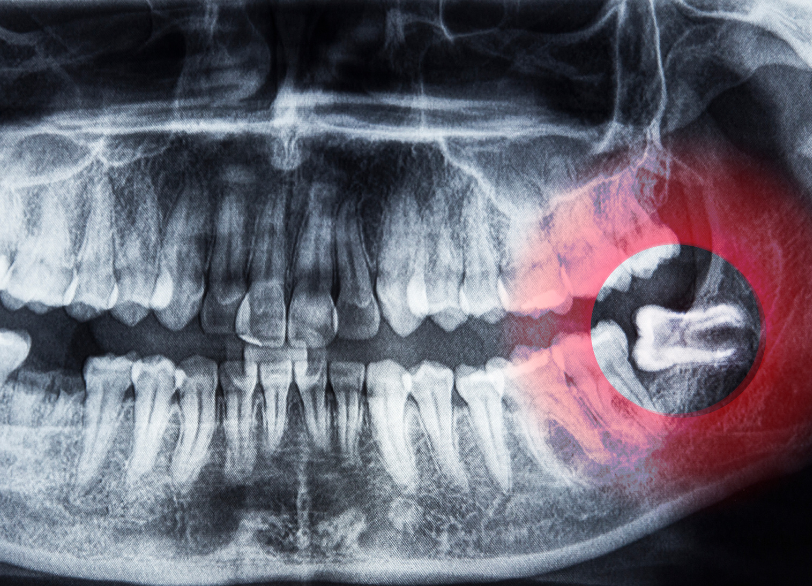

十分なスペースがないために、親知らずは様々な不自然な生え方をしてしまいます。

- 斜めに生える

- 横向きに生える(水平埋伏)

- 一部だけが歯肉から出ている(半埋伏)

- 骨の中に完全に埋まっている(完全埋伏)

このような不自然な生え方をすると、お口の中に様々なトラブルを引き起こす原因となります。

特に、下の親知らずのすぐ近くには「下歯槽神経(かしそうしんけい)」という、下唇の感覚などを司る非常に重要な神経が通っています。

従来の二次元のレントゲン写真だけでは、この神経と親知らずの根との正確な位置関係を把握することは困難です。

当院では、抜歯の前に必ず歯科用CTによる撮影を行いこの神経と歯の根との距離や位置関係を、三次元的にそしてミリ単位で正確に把握します。

この情報を基に、神経を傷つけるリスクを限りなくゼロに近づけるための安全な抜歯計画を立案します。